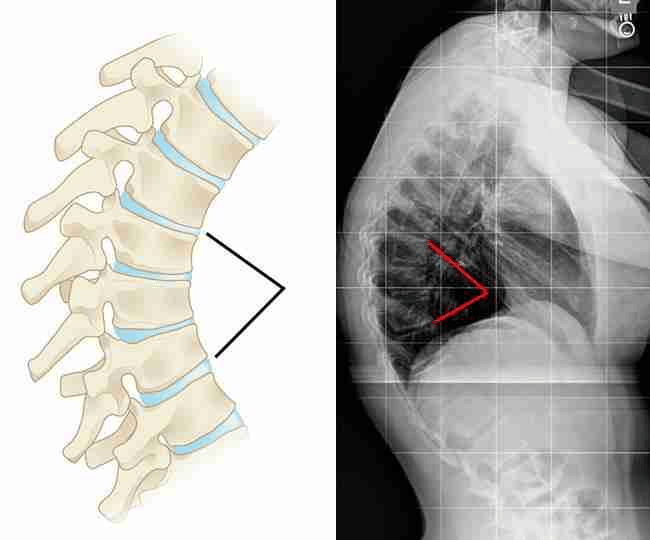

Kyphosis, colloquially known as “hunchback” or “round back,” is a spinal condition characterised by an excessive forward curvature of the upper back. This can lead to a noticeable rounding of the spine, causing various symptoms and discomfort.

To confirm and assess kyphosis, imaging tests are commonly used, such as X-rays and MRIs. X-rays provide detailed spine images to measure curvature, while MRIs offer more comprehensive views, including soft tissues and potential underlying conditions.